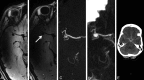

Results: We included 57 patients with 65 unruptured intracranial aneurysms. After a median follow-up of 27 months (interquartile range, 20-31 months), growth (n = 2) or rupture (n = 2) was observed in 4 of 19 aneurysms (21%; 95% CI, 6%-54%) with wall enhancement and in zero of 46 aneurysms (0%; 95% CI, 0%-8%) without enhancement (risk difference, 21%; 95% CI, 3%-39%).

Conclusions: Gadolinium enhancement of the aneurysm wall on MR imaging is associated with an increased risk of aneurysm instability. The absence of wall enhancement makes it unlikely that the aneurysm will grow or rupture in the short term. Larger studies are needed to investigate whether aneurysm wall enhancement is an independent predictor of aneurysm instability.